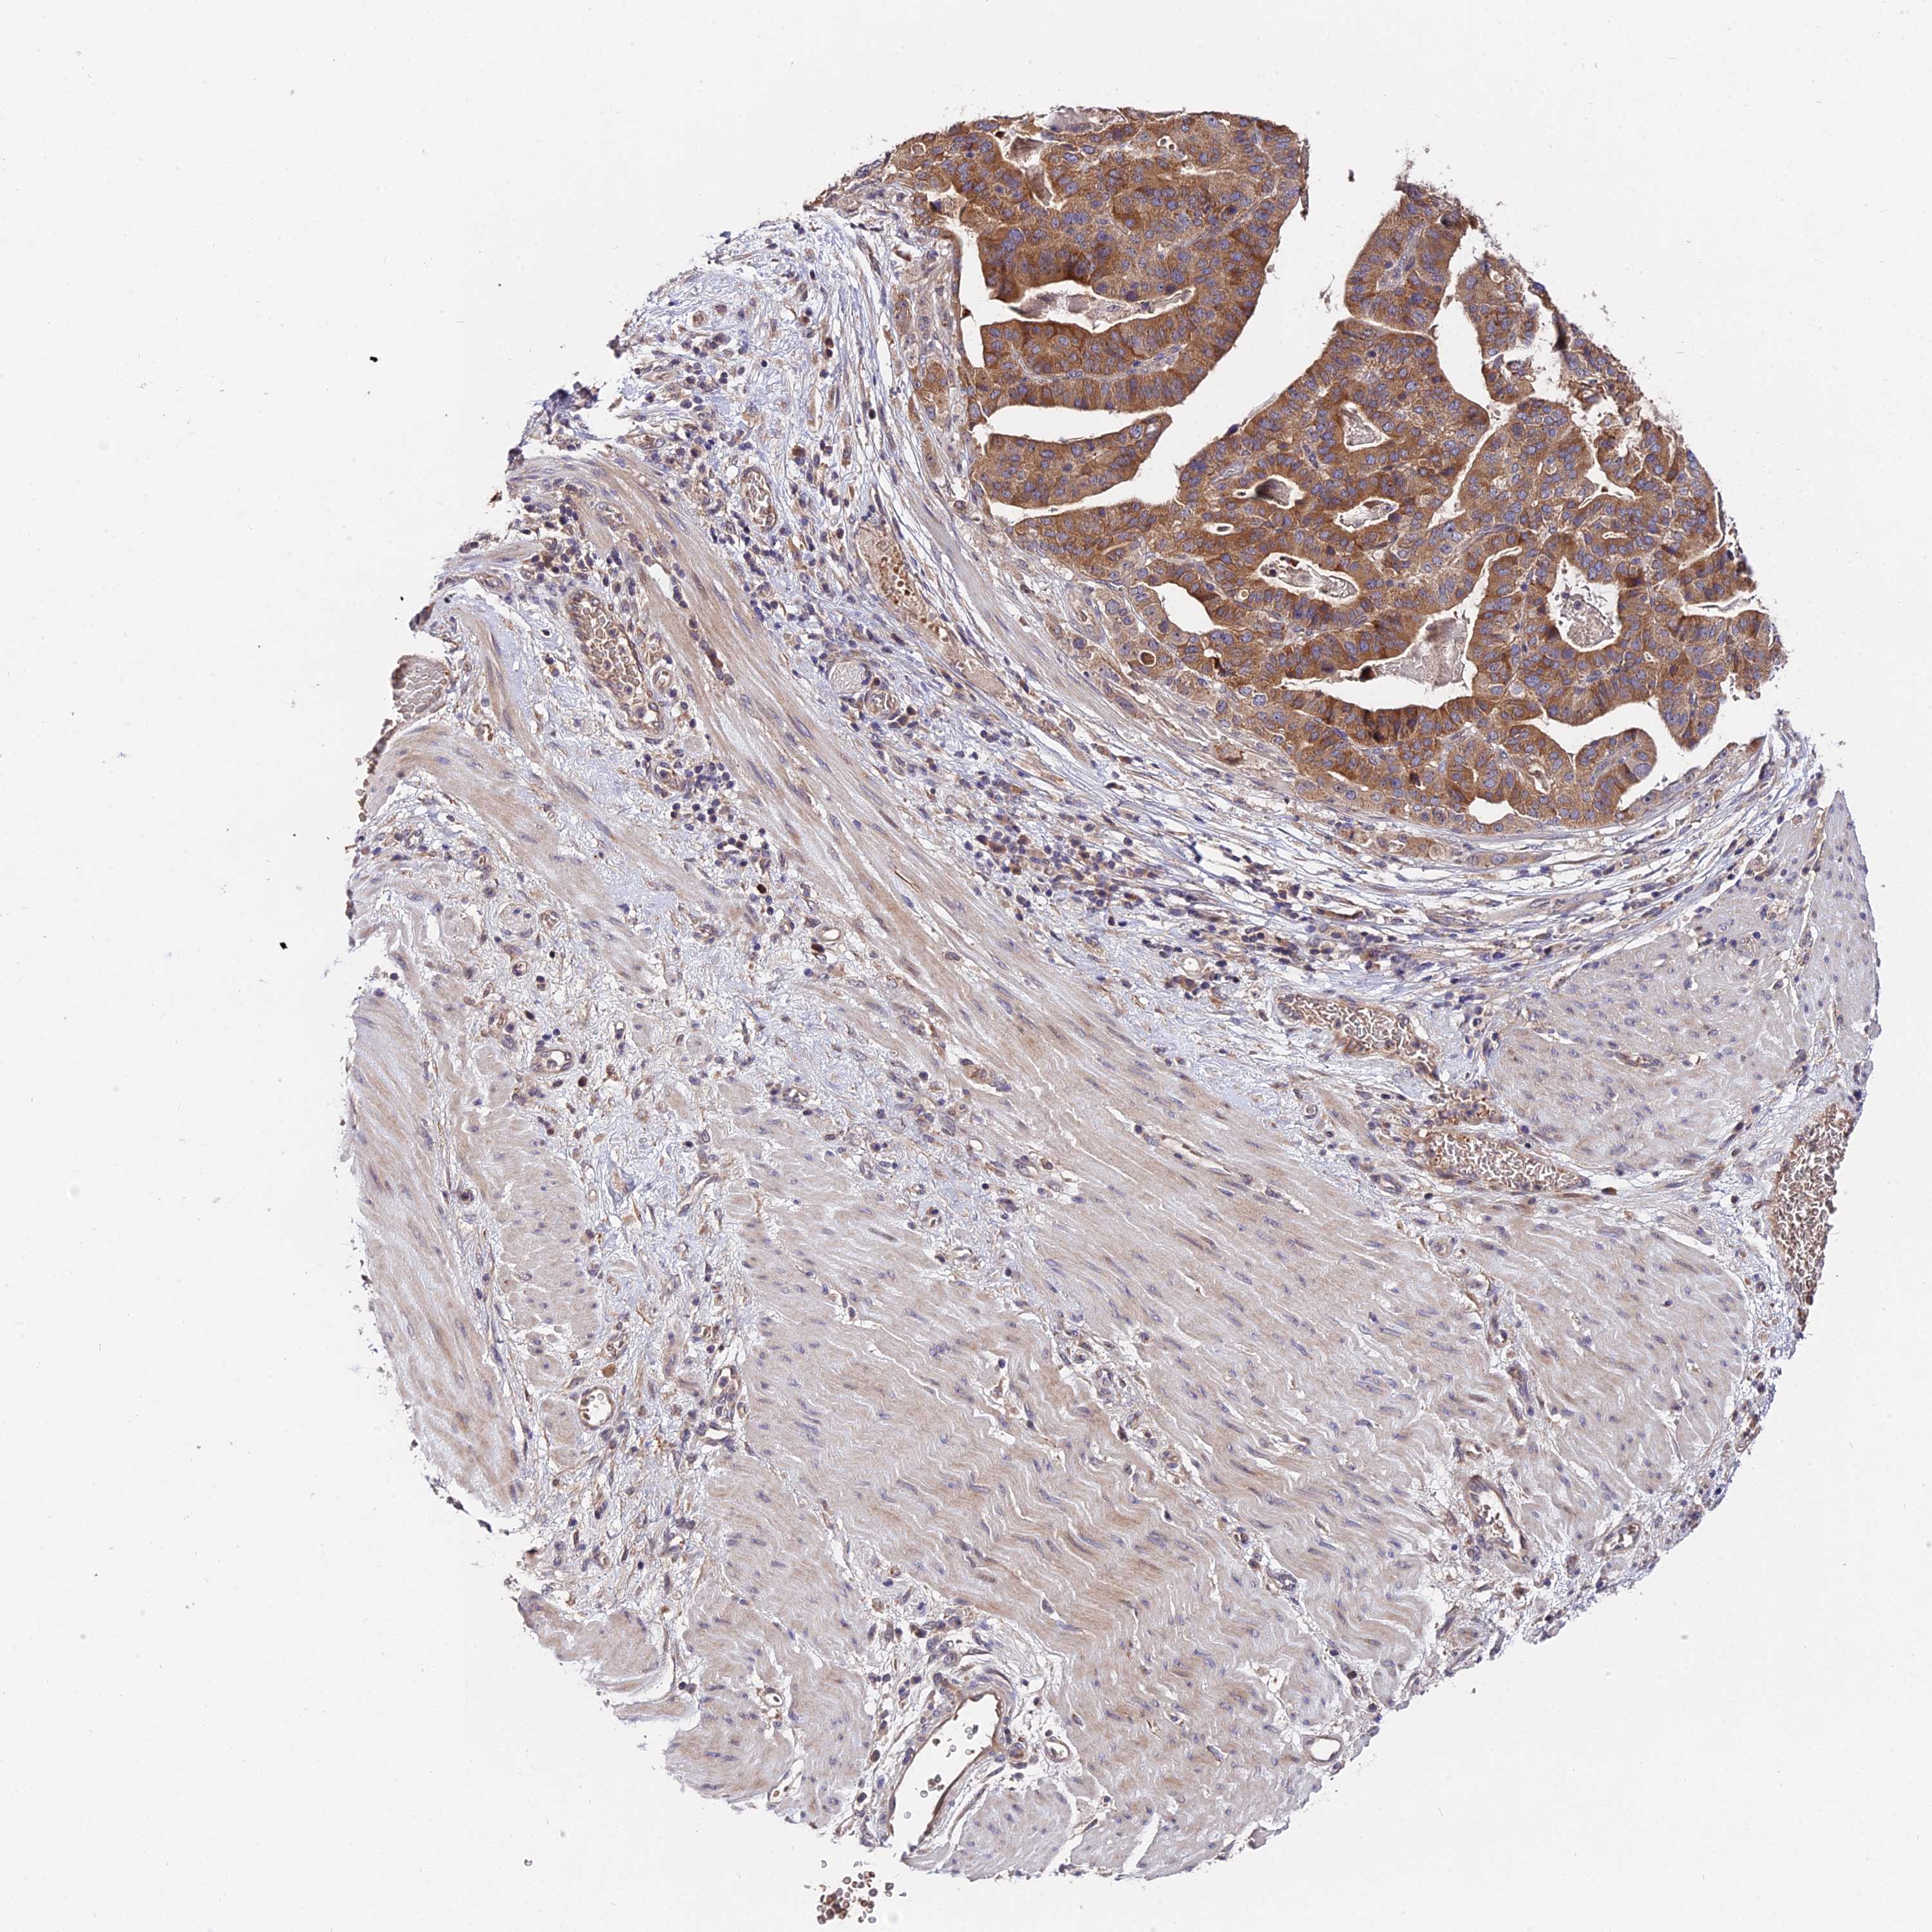

STOMACH CANCER - Protein expressioni

A mouse-over function shows sample information and annotation data. Click on an image to view it in a full screen mode. Samples can be filtered based on level of antibody staining by selecting one or several of the following categories: high, medium, low and not detected. The assay and annotation is described here.

Note that samples used for immunohistochemistry by the Human Protein Atlas do not correspond to samples in the TCGA dataset.

Antibody stainingi

Antibody staining in the annotated cell types in the current human tissue is reported as not detected, low, medium, or high, based on conventional immunohistochemistry profiling in selected tissues. This score is based on the combination of the staining intensity and fraction of stained cells.

Each image is clickable and will lead to virtual microscopy that enables deeper exploration of all samples and also displays staining intensity scores, fraction scores and subcellular localization as well as patient and tissue information for each sample.

Antibody HPA041130

Antibody HPA041380

Staining

High

Medium

Low

Not detected

Intensity

Strong

Moderate

Weak

Negative

Quantity

>75%

75%-25%

<25%

None

Location

Nuclear

Cytoplasmic/membranous

Cytoplasmic/membranous,nuclear

Adenocarcinoma, NOS